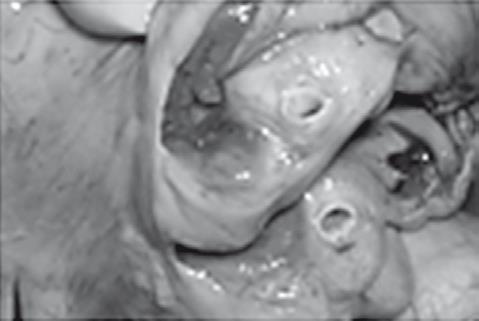

Иллюстрация к книге — Неалкогольная жировая болезнь печени [i_041.jpg]

Хронический стеатогепатит

Рис. 38. Летальный случай пациентки с острым отравлением алкоголем